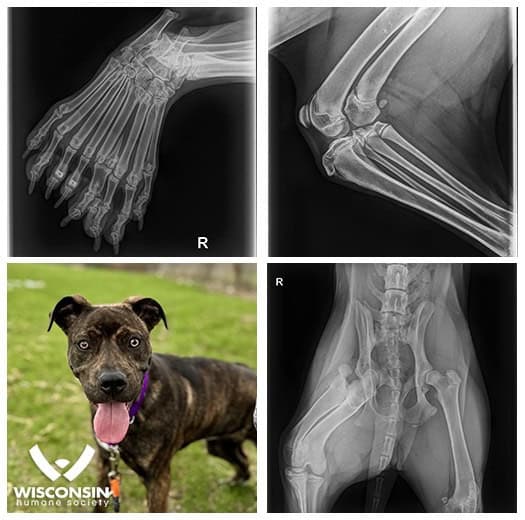

Dimelia, characterized by bone duplication, is exceptionally rare in dogs. Bella’s X-rays reveal an extra femur, two tibias, two fibulas, and nine toes on her hind leg.

She’s the first documented case at the Wisconsin Humane Society and one of the few worldwide. This condition doesn’t hinder Bella’s mobility or zest for life.